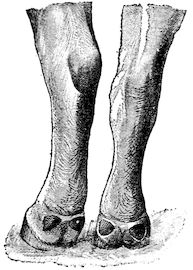

Fig. 1.—Rachitis in a young goat.